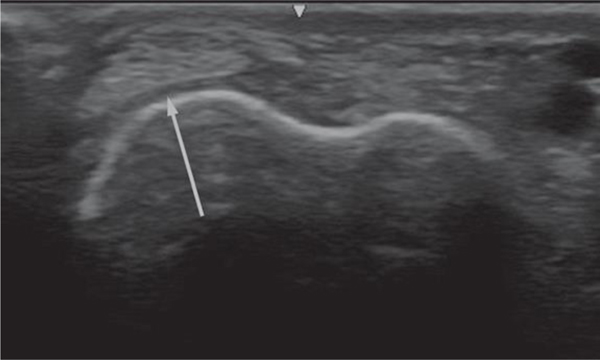

The study results identified two ultrasound acoustic windows characterized by the highest predictive value for alteration of the wrist's structure. Study results indicated an impairment of the distal median nerve in structure and mobility and impairment of the distal tendon of the muscle extensor carpi ulnaris that included dislocation and frank damage.

This study identified at least two acoustic windows that should be assessed with ultrasound studies on larger groups and in prospective periodical health surveillance of dairy workers. The study confirmed the wrist was at risk for biomechanical stress among workers conducting milking tasks in the dairy parlors.